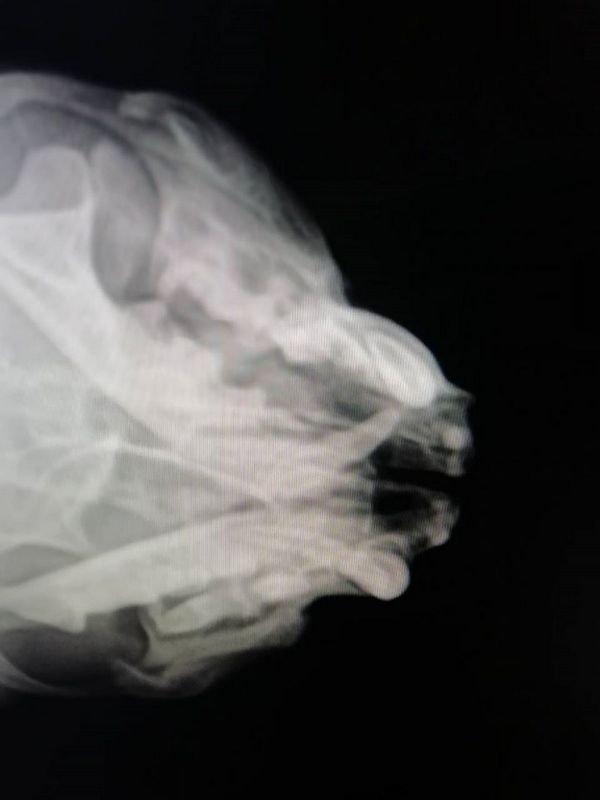

Закрытая черепно-мозговая травма с отеком головного мозга, переломом челюсти, разрывом барабанных перепонок, истощением, обезвоживанием, травмой позвоночника и судорожным синдромом - все это обнаружили у котика. Под свою временную опеку его взял мини-приют "Мы за право на жизнь". Перед клиникой за первоначальное лечение Цитрамона уже висит долг - около 500 гривен. Но коту нужна срочная консультация у невролога и МРТ-обследование позвоночника.